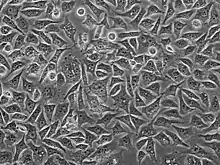

PC3 (PC-3) is a human prostate cancer cell line used in prostate cancer research and drug development. PC3 cells are useful in investigating biochemical changes in advanced prostate cancer cells and in assessing their response to chemotherapeutic agents. PC3 cells are also used to study viral infection in mammalian cells that exhibit an immune response[1]

The PC3 cell line was established in 1979 from bone metastasis of grade IV of prostate cancer in a 62-year-old Caucasian male.[2] These cells do not respond to androgens, glucocorticoids or fibroblast growth factors,[3] but results suggest that the cells are influenced by epidermal growth factors.[4] PC3 cells can be used to create subcutaneous tumor xenografts in mice to investigate the tumor environment and therapeutic drug functionality.

PC3 cells have high metastatic potential compared to DU145 cells, which have a moderate metastatic potential, and to LNCaP cells, which have low metastatic potential.[5] Comparisons of the protein expression of PC3, LNCaP, and other cells have shown that PC3 is characteristic of small cell neoendocrine carcinoma.[3]